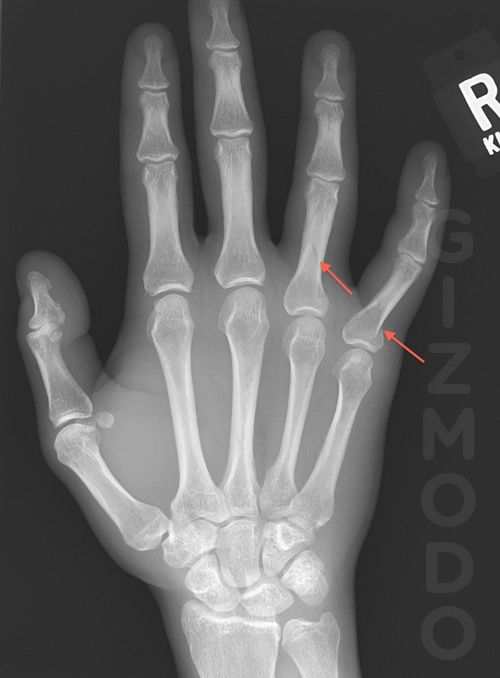

El responsable de la rotura que vemos en la imagen es el God of War III según el médico:

“Tuve un paciente que estaba tan ocupado con el juego God Of War III que giró sobre su mano con la rodilla y se rompió dos dedos. Adjunto la radiografía (con los datos del paciente eliminados y flechas apuntando a sus fracturas). Es la primera vez que veo una lesión por jugar hasta el extremo.”